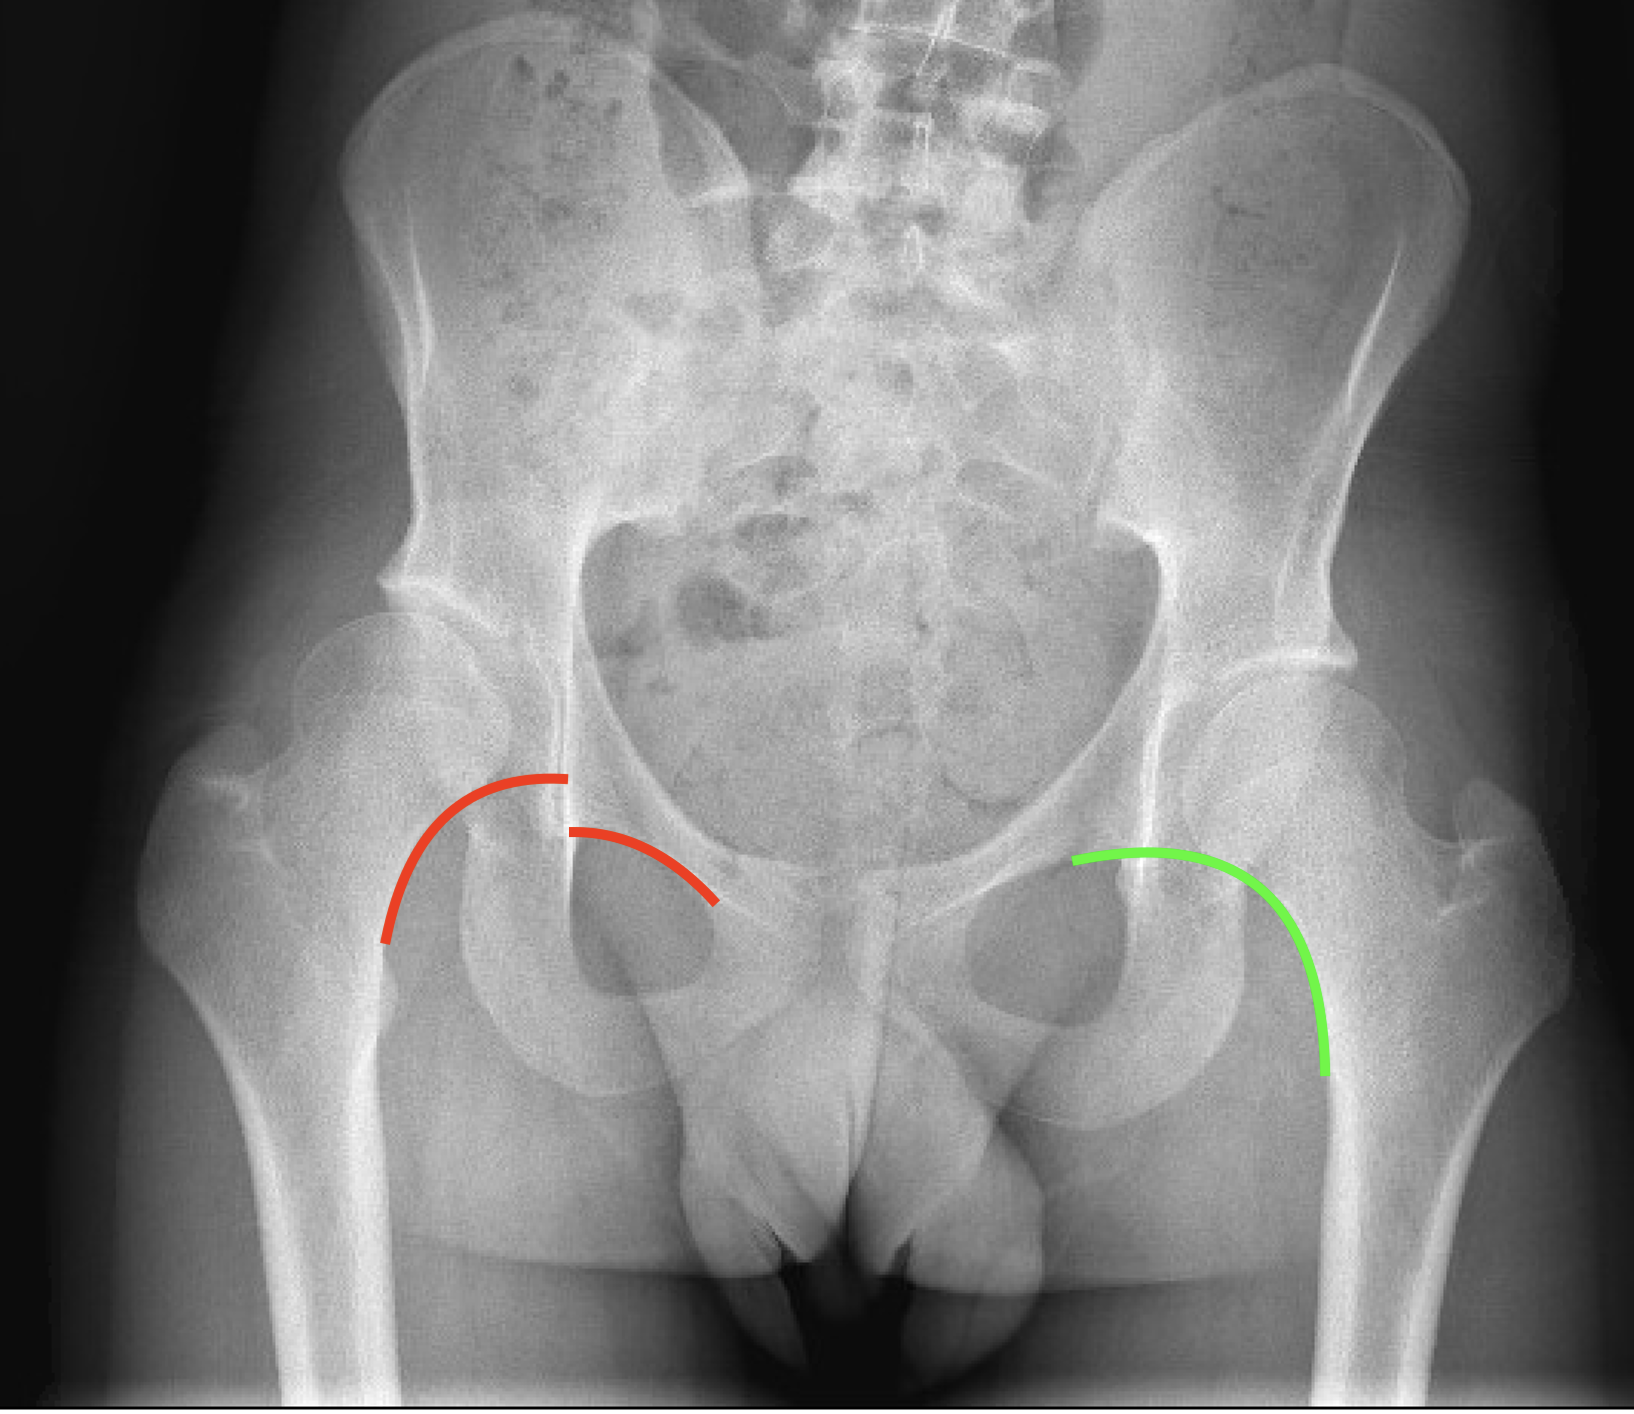

Shenton lijn

- Rechts op de foto zie je een doorlopende Shenton lijn: groen.

- Links op de foto zie je een doorbroken Shenton lijn: rood.

Als de Shenton lijn doorbroken is, wil dit zeggen dat de heupkop iets uit de kom schuift. Het is een reden om de heup zeker binnen de 6 maanden te opereren. Als dit niet gecorrigeerd wordt, zal er snelle slijtage optreden. Vaak moet dan voor de leeftijd van 30 jaar een totale heupprothese worden geplaatst.